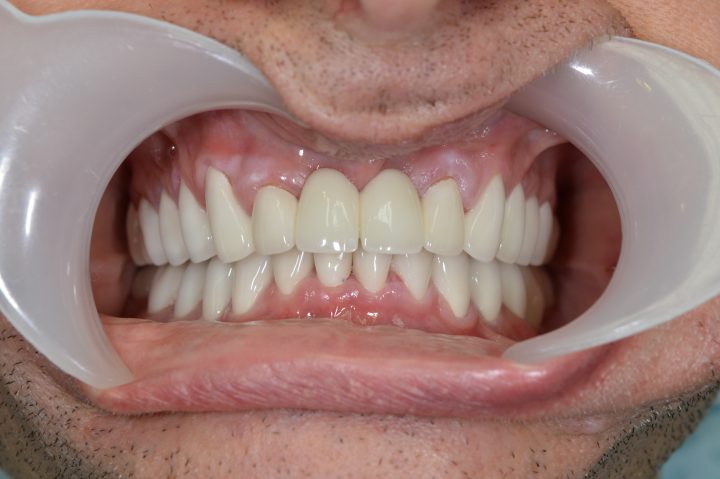

Mark ist ein englischer Patient bei uns, der sich in seinem ganzen Leben nach weißen Zähnen gesehnt hat. Sein Fall ist unregelmäßig, weil er früher eine andere ungarische Zahnklinik besucht, hat, wo er Implantate bekommen hat. Aber er war mit der Patientbetreuung nicht zufrieden.

Auf den Rat von seinem Freund hat er so entschieden, dass er die Behandlung in der Zahnklinik Centrocc Dental beenden möchte. Er hat diese Entscheidung nicht bereut, und hat die Klinik seinen alten Traum verwirklicht.

Auf seine Implantate haben wir durch Frau Dr. Erdélyi insgesamt 24 Stück Metallkremaik Kronen bearbeitet.